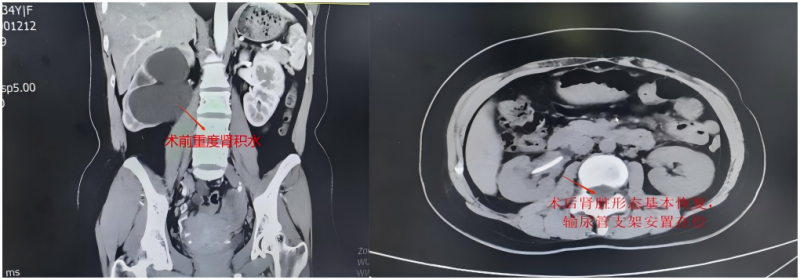

依托医院多学科协作平台,在党支部及医务科的统筹指导下,妇产科、泌尿科、放射科、重症医学科、麻醉科等多科室党员和技术骨干积极参与,开展多次术前联合讨论。术前CT显示患者子宫增大、双侧卵巢囊肿、盆腹腔重度粘连,同时伴有一侧肾脏明显长大、肾盂重度扩张。手术迫在眉睫,团队围绕“彻底切除病灶、最大限度保护生育功能、精确修复输尿管、解除肾积水”的整体目标,精心准备手术方案,并制定多套应急预案,全力保障手术安全。

手术期间中,党员专家们以精湛技艺紧密配合:妇产科马超主任团队耐心细致分离盆腔粘连,完整的切除了异位病灶,为后续操作扫清障碍;泌尿外科刘强主任团队精准定位受损输尿管,实施精细修复重建。整个手术过程中,党员同志冲锋在前、严谨细致,凭借扎实的专业功底和无畏的担当精神,顺利完成了这场高难度手术。术后复查CT显示,患者肾脏形态基本恢复正常,原重度扩张的肾盂已完全回缩,经团队精心照护,患者术后一周顺利康复出院。